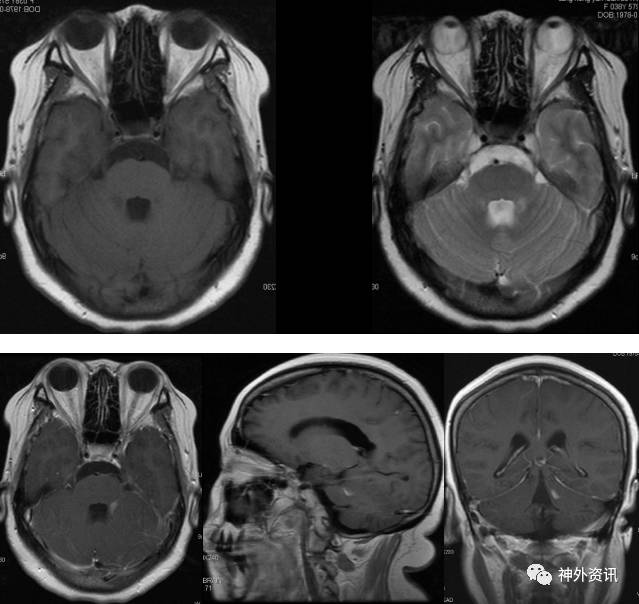

头颅MRI平扫加增强:左侧桥臂异常信号灶,范围约1.0*0.7cm*1.1cm,呈等T1稍长T2信号,增强后强化明显。诊断:左侧桥臂异常强化灶,考虑脱髓鞘病变可能。(图2)。

图2. MRI检查:左侧桥臂异常信号灶,范围约1.0*0.7cm,T1WI呈等信号,T2WI呈稍高信号,增强后明显强化。

入院后神经内科予以脱水、激素及对症支持治疗,患者头痛稍缓解,视力、视野无明显改善。1月后复查头颅MRI增强,提示左侧桥臂病灶无明显变化(图5)。依然考虑左侧桥臂病灶为脱髓鞘病变可能性大。因颅内高压缓解不明显,请我科会诊后转入我科。

图5. MRI复查:左侧桥臂异常信号灶,T1WI呈等信号,T2WI呈稍高信号,增强后明显强化,较前片无明显变化。